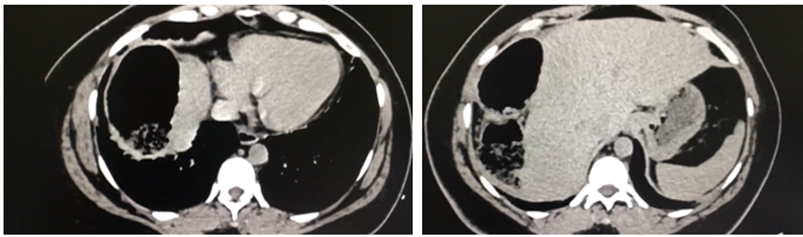

Se realizo una radiografía abdominal que revela la presencia de pseudoneumoperitoneo (Fig.1). Posteriormente, una tomografía computarizada abdominal evidencia colon derecho sobre la superficie hepática (Fig.2).

Su diagnóstico requiere estudios de imagen que confirmen la anomalía, cumpliendo los siguientes tres criterios:

El hemidiafragma derecho debe estar elevado por el intestino.

Debe simular un neumoperitoneo.

El borde superior del hígado debe encontrarse por debajo del diafragma izquierdo, tal como se evidenció en el caso presentado.2